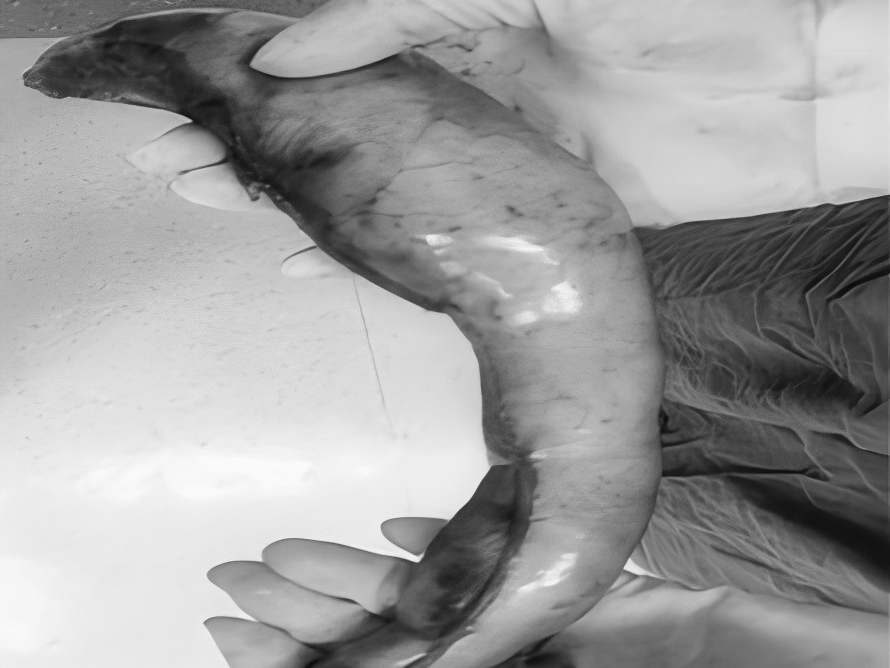

一名女性患者长期受到下腹部坠胀、排便不适等症状困扰,近期发现盆腔内存在肿物,严重影响其生活质量,为寻求进一步诊治,她前往贵州航天医院普外科就诊,经核磁共振(MRI)检查提示:盆腔内直肠与骶骨之间有一个“骶前囊肿”。由于该囊肿位置深,且与周围重要的神经和血管关系密切,若采用传统手术不仅创伤大,还伴随一定的风险。 面对这一棘手难题,普外科立即组织了麻醉科、医学影像科、妇科、重症医学科在内的多学科专家会诊(MDT)。经专家团队详细评估,与患者及家属充分沟通后,为患者制定并成功实施了“腹腔镜下骶前囊肿切除术”。术后恢复良好,不久便康复出院。 【疾病科普|什么是骶前囊肿?】 骶前囊肿,可以理解为生长在骨盆最深处、直肠后方的一个囊性肿物。由于它“躲藏”的位置非常特殊,四周紧邻着控制排便和感觉的重要神经与血管,因此被视为盆腔外科手术中的一个难点。 它可能带来哪些影响? 1.随着囊肿逐渐增大,可能会压迫直肠,引起排便困难或坠胀感。 2.压迫骶神经,可能导致腰骶部或会阴区的酸胀、疼痛。 3.囊肿本身也可能发生感染,形成脓肿,加重不适。 【技术介绍|腹腔镜下骶前囊肿切除术】 对于骶前囊肿这类较深的病灶,腹腔镜下骶前囊肿切除术提供了一种更为微创、便于操作的解决方案。 它是如何进行的? 医生仅通过腹部几个约0.5-1厘米的小孔,其中一个孔放入带高清摄像头的腹腔镜,将盆腔内的景象放大并清晰地投射到屏幕上,如同给了医生一双进入体内的“眼睛”。其他几个小孔则伸入细长的专用手术器械。医生看着屏幕,遥控这些器械,在清晰的视野下精细地分离并完整切除囊肿。 腹腔镜微创手术的特点包括: ▶创伤较小:避免了传统手术的长切口,体表疤痕小。 ▶视野清晰:放大后的图像让医生能更清楚地分辨囊肿与周围重要结构。 ▶操作精准:有助于更完整地切除囊肿,并尽力保护盆腔神经功能。 ▶恢复较快:因手术创伤小,患者术后疼痛感更轻,下床活动早,住院时间也可能缩短。 注:本文旨在进行健康科普,分享医疗案例与科普知识,不能替代任何专业的医疗建议。如有任何健康问题,请务必及时咨询并遵从专业医生的诊疗意见。 贵州航天医院普外科专家简介 高大勇 普外科(肛肠外科)学科带头人、名誉主任,主任医师、教授 临床擅长:对中西医结合诊治肛肠学科各种常见病、多发病及疑难杂症等具有丰富的临床经验。 原遵义市第一人民医院(遵义医科大学第三附属医院)、遵义市中医院肛肠科主任。中华中医药学会肛肠分会常委,全国中医肛肠学科名专家,中国健康促进与教育协会肛肠分会常委,中国康复医学会肛肠疾病康复专业委员会常委,中国民间中医医药研究开发协会肛肠分会副秘书长,中国医师协会中西医结合肛肠医师专业委员会常委,国家二级心理咨询师,贵州省第一批中医名医工作指导老师,遵义市名中医,遵义市肛肠学会会长,遵义市肛肠质控中心名誉主任,遵义市中西医结合学会名誉会长,遵义市健康科普专家,原贵州省中西医结合学会肛肠分会副主任委员、贵州省中医肛肠质控中心副主任、遵义市医学会医疗鉴定委员会专家、遵义市卫生系列高级评委。发表论文30余篇,主编和参编医学著作5本,主持省级科研课题2项、市级科研课题2项、院级科研课题1项。 梁 跃 普外科党支部书记、主任,主任医师 临床擅长:对普外科各类肿瘤手术具有丰富的临床经验。 毕业于遵义医学院,遵义市医学会小儿外科学分会常务委员,遵义市肛肠协会理事,遵义市医学会核医学分会(第二届)委员会委员;荣获第三期“黔医人才计划”优秀学员称号;主持市级课题1项,完成省级课题1项,在国内各类刊物上发表论文10余篇。 钱科洪 民盟盟员,普外科副主任医师 临床擅长:从事普外科临床工作30余年,对各类普外科疾病的诊治、乳腺、甲状腺、胃十二指肠、结直肠等疾病及疑难杂症具有丰富的临床经验。 毕业于遵义医学院临床医疗系,2009年前往中山大学附属第一医院微创外科进修学习,在国内各专业期刊发表论文数篇。 贵州航天医院普外科简介 基本情况 贵州航天医院普外科成立于1968年,前身属于原航天部O61基地3417医院外一科,1998年3417医院、3427医院合并后更名为普外科,下设胃肠外科、肛肠外科2个亚专业科室,拥有在全市较为先进的专科设备和技术,是中国疝病专科联盟单位,贵州医科大学附属医院胃肠外科专科联盟单位。开放床位40张,配备医护人员21人。 专科特色 普外科致力于胃肠及肛肠疾病的外科临床诊治及科研,以腹腔镜微创外科技术为本,形成以快速康复治疗胃肿瘤、结直肠肿瘤、小肠肿瘤、直肠脱垂、肥胖病、急腹症、各类疝、痔、瘘等专科特色,同时注重胃肠疾病尤其是结直肠恶性肿瘤的基础研究和临床转化研究,总体诊断和治疗水平在区域同级医院居于领先水平。 开展手术:腹腔镜下胃癌根治术,腹腔镜下袖状胃切除术,腹腔镜下胃肠道间质瘤切除术,腹腔镜下结、直肠癌根治术,胃癌、结直肠癌的精准治疗,腹腔镜下小儿疝气、成人疝修补术,腹腔镜下阑尾手术,内痔的硬化注射治疗及痔疮的微创治疗:ATH、PPH、TST,直肠脱垂的各种手术治疗,难治性伤口VSD技术,鼻胃肠管、肠梗阻导管置入术,肛肠术后间歇性导尿技术,并引进了中医适宜技术,也为各种化疗患者提供输液港安装,提高患者就医体验。 腹腔镜下腹股沟疝 无张力修补术 腹股沟疝里金斯坦 (Lichtenstein)手术 PPH微创术治疗环状混合痔 黏连性或炎性肠梗阻-肠梗阻导管 腹腔镜袖状胃切除 腹腔镜阑尾切除术 腹腔镜阑尾肿瘤切除术 腹腔镜下结肠癌根治术 诊疗范围 胃肿瘤、结直肠肿瘤、小肠肿瘤、肥胖症、各类急腹症、腹部外伤、腹壁疝、便秘、直肠脱垂、痔疮、肛瘘、肛裂等胃肠、肛肠外科疾病。 END